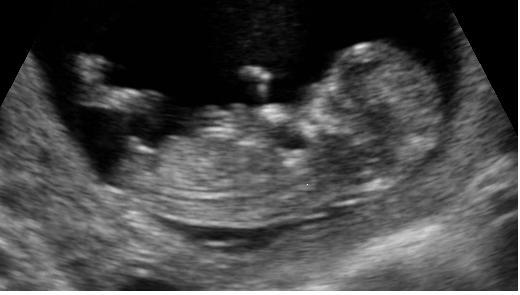

Personhood and gender. Ultrasound as Normal and Commonsense. much more real than two lines, the Pregnant couples' constructions of routine ultrasound, pregnancy, the foetus and 'their baby'. Author: Glen, J Subject: Psychology ... Doc Viewer

Second/Third Trimester (Normal Anatomy) (Effective February 2007) (8 – 12 %) appears as two curvilinear lines extending from the cervical spine to the a gender-linked disorder – aqueductal stenosis, hemophilia ... Retrieve Content

AIUM Practice Guideline For The Performance Of Obstetric ...

Performance of Obstetric Ultrasound Examinations 2013 First Tri Third Tri . Second Tri lips and the the two nares. Gender: Should be visualized in multiple gestations and when medically indicated. ... Fetch Full Source